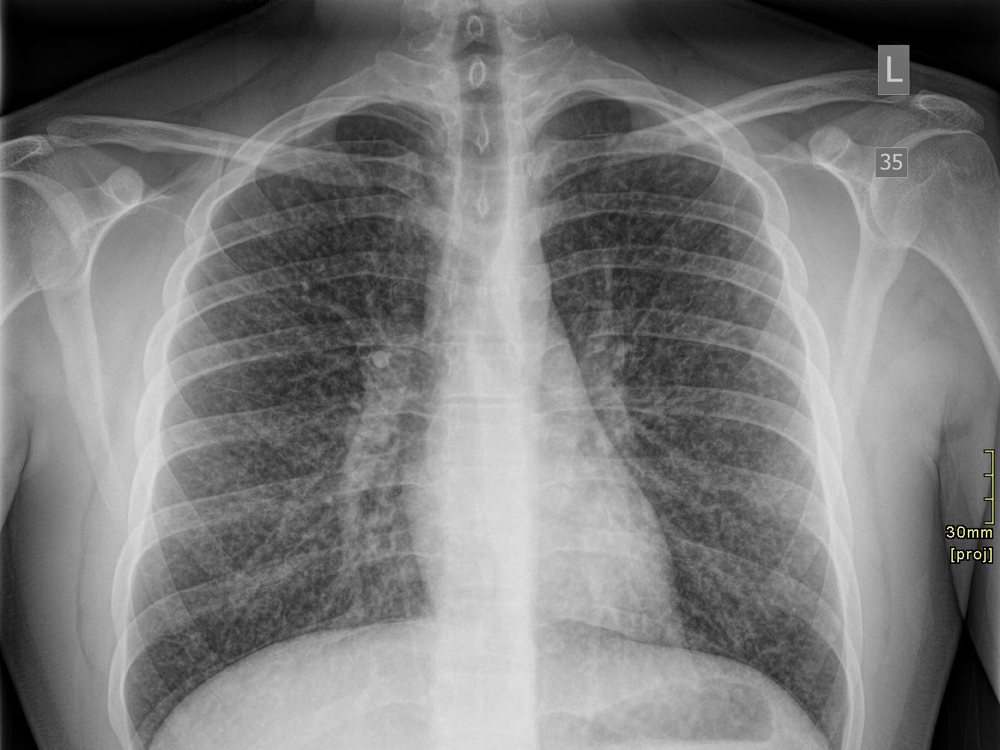

Chest radiography before and after steroids treatment. Top left and Rattly Chest After Vaping These include shortness of breath, fever and chills, cough, vomiting, diarrhea, headache, dizziness, rapid heartrate and chest pain. People who vape who develop constrictive bronchiolitis may develop symptoms like: Recently, a multistate epidemic has emerged. Your doctor will evaluate your history of e. Sep 19, 2019, 9:18 am pdt. Some evidence of the health risks showed up in 2019, when. Rattly Chest After Vaping.